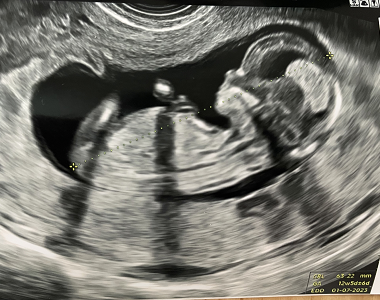

Přinášíme vám oblíbený seriál, ve kterém budeme sledovat náročné těhotenství maminky Katky doslova v přímém přenosu. Maminka Katka se s vámi podělí o své pocity, nálady, události aktuálních týdnů těhotenství. Nebudou chybět ani těhotenská vyšetření. Včetně jedinečného pohledu Katky na jejich rodinu, rodičovství jako partnerství a speciálně popíše i pohled chlapa na rodičovství. Tentokrát se máte opět na co těšit!